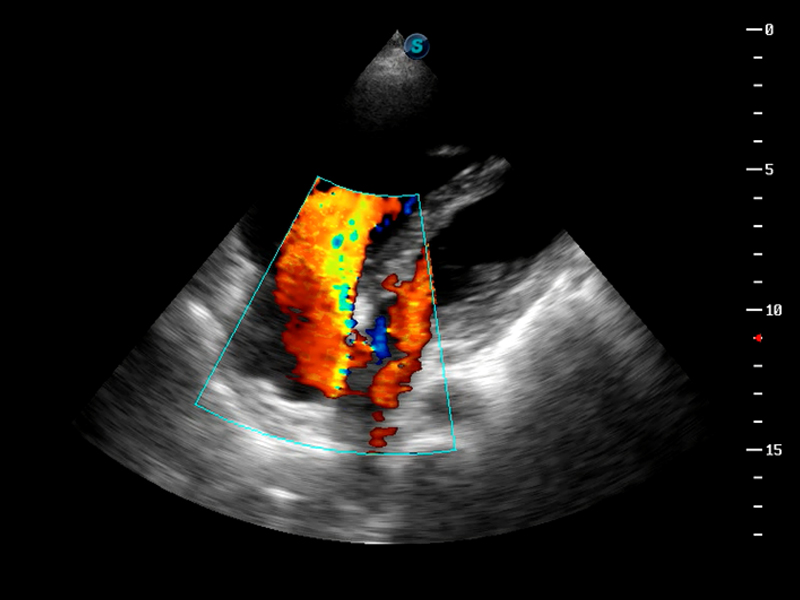

S9便携式彩色多普勒超声诊断仪是狗万官方网站研发的高端便携彩超设备,外观设计新颖、产品性能卓越。S9在便携超声领域采用了突破传统的触摸屏交互设计,并以先进的软件硬件技术和设计理念,为您带来清晰的图像质量、稳定的工作性能和便捷的操作体验。

VIS平台设计

μ-Scan微米成像

脉冲反相谐波成像

TDI组织多普勒成像

AutoC智能血流追踪